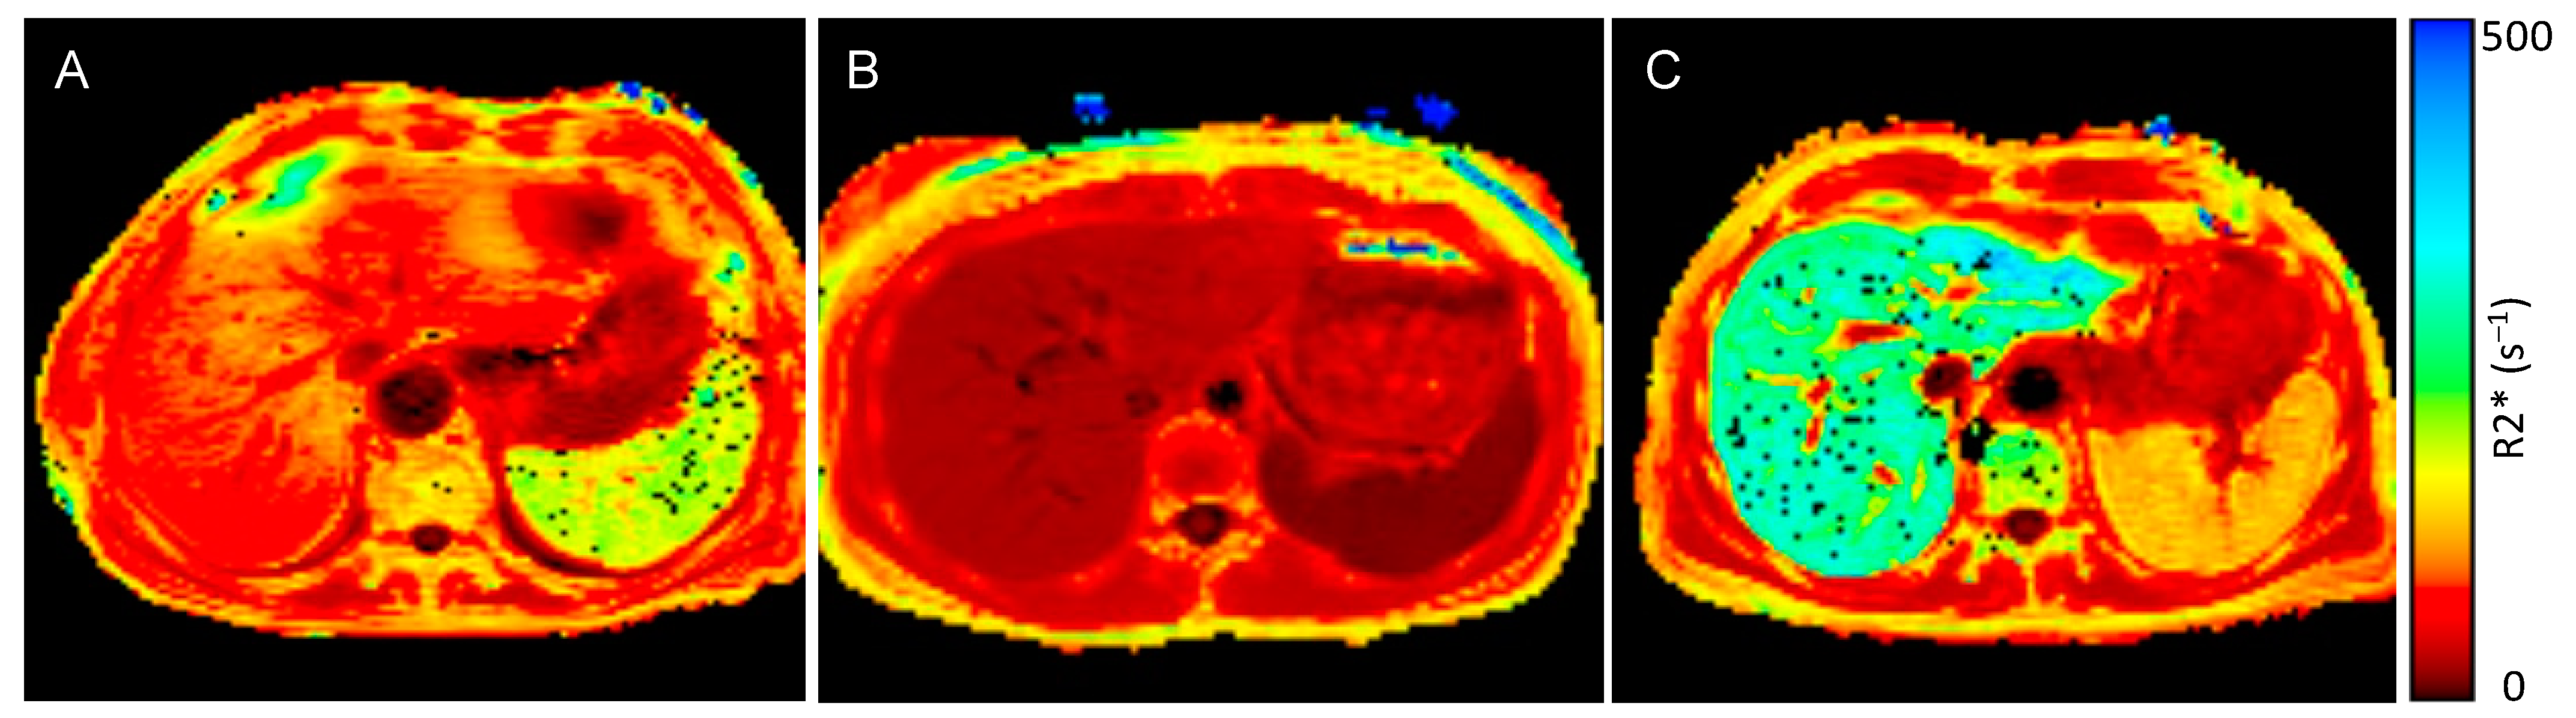

3.2. Tissue Iron Distribution Measured by MRI R2* Sequence

| Spleen R2* [s−1] | 19.3 (15.5–33.0) | 119.8 (78.5–188.2) | <0.001 |

| Liver R2* [s−1] | 36.1 (31.9–39.1) | 90.1 (54.5–110.0) | <0.001 |